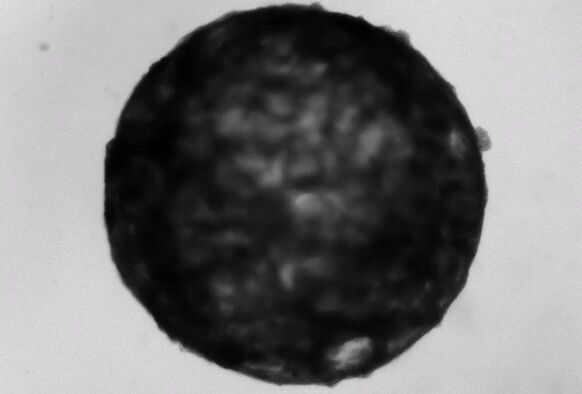

图片来源:The Mendjan Lab视频截图

发育1周后,类器官在结构上相当于25天胚胎的心脏。在这个阶段,心脏只有一个心室,这将成为成熟心脏的左心室。类器官直径约为2毫米,包括这一发育阶段常见的主要细胞类型:心肌细胞、上皮细胞、成纤维细胞和心外膜。它们也有一个清晰的心室,每分钟跳动60到100次,这与相同年龄的胚胎心脏的速率相同,研究小组在《细胞》杂志上报道。

“当我第一次看到它的时候,我很惊讶这些心室可以自己形成。”主要作者、奥地利科学院分子生物技术研究所的干细胞生物学家Sasha Mendjan说,“令人惊奇的是,你马上就能看到实验是否成功,类器官是否正常工作,因为它会跳动——不像其他类器官。”